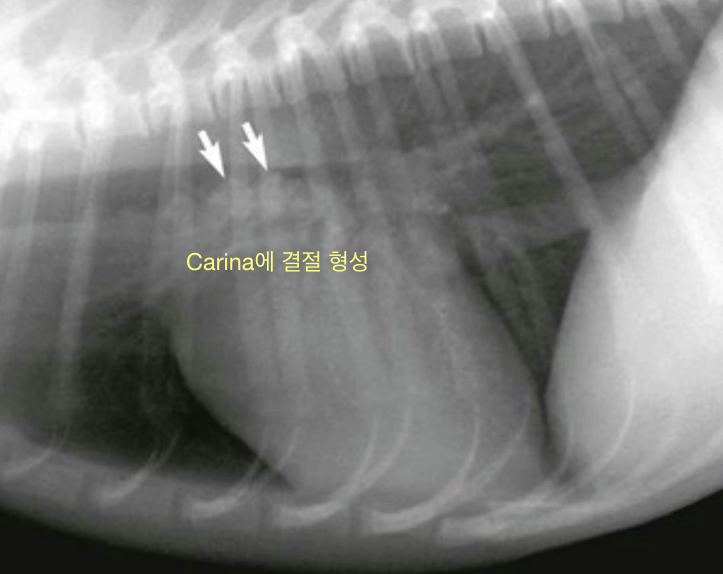

➕ Oslerus Osleri (기생충)

- Carina나 bronchi에 서식.

- 초기에는 CIRDC와 구분 어려움. but carina에 결절이 형성되며 결국 airway obstruction을 나타내는 차이점.

- 방사선 촬영 - carina의 nodules

- bronchoscopy로 결절 가장 잘 보임.

- tracheal wash에서 ova or larvae 관찰.